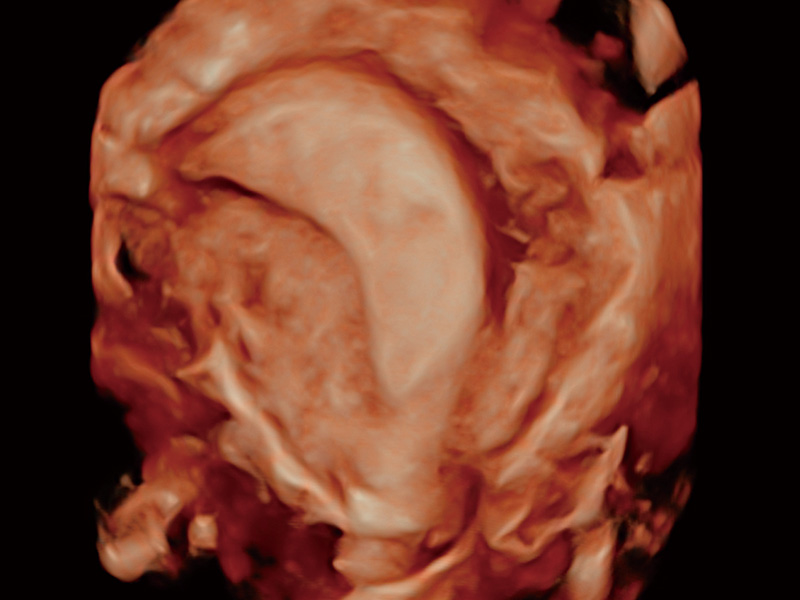

腔内容积探头

腔内三维成像技术获得显著提升,超大扇角在满足日常基础扫查的同时,支持卵泡自动测量及多种三维渲染模式,为您提供更多的诊断信息,尤其是在子宫畸形的诊断,内膜及肿瘤占位观测中起到了重要的作用。

中央型宫腔粘连